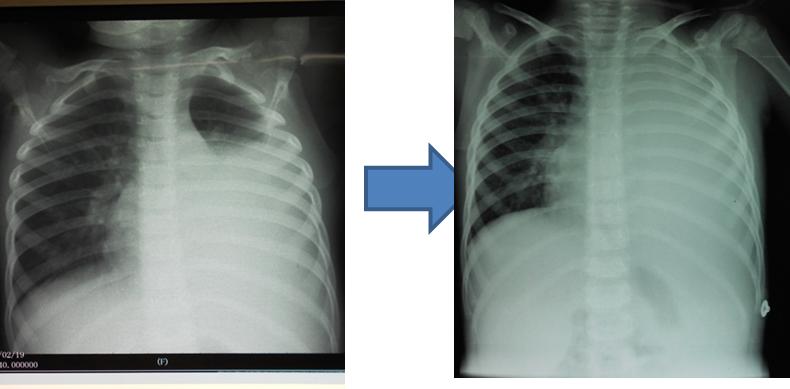

刚刚在医院给娃拍的肺部片子,医生帮我看看是不是肺炎

对比两图,胸片(下图左)通常可以看到上肺单侧或双侧的阴影,而肺部ct

学龄期学龄前期儿童,持续高热时间长,咳嗽剧烈,肺部拍片有大片的阴影